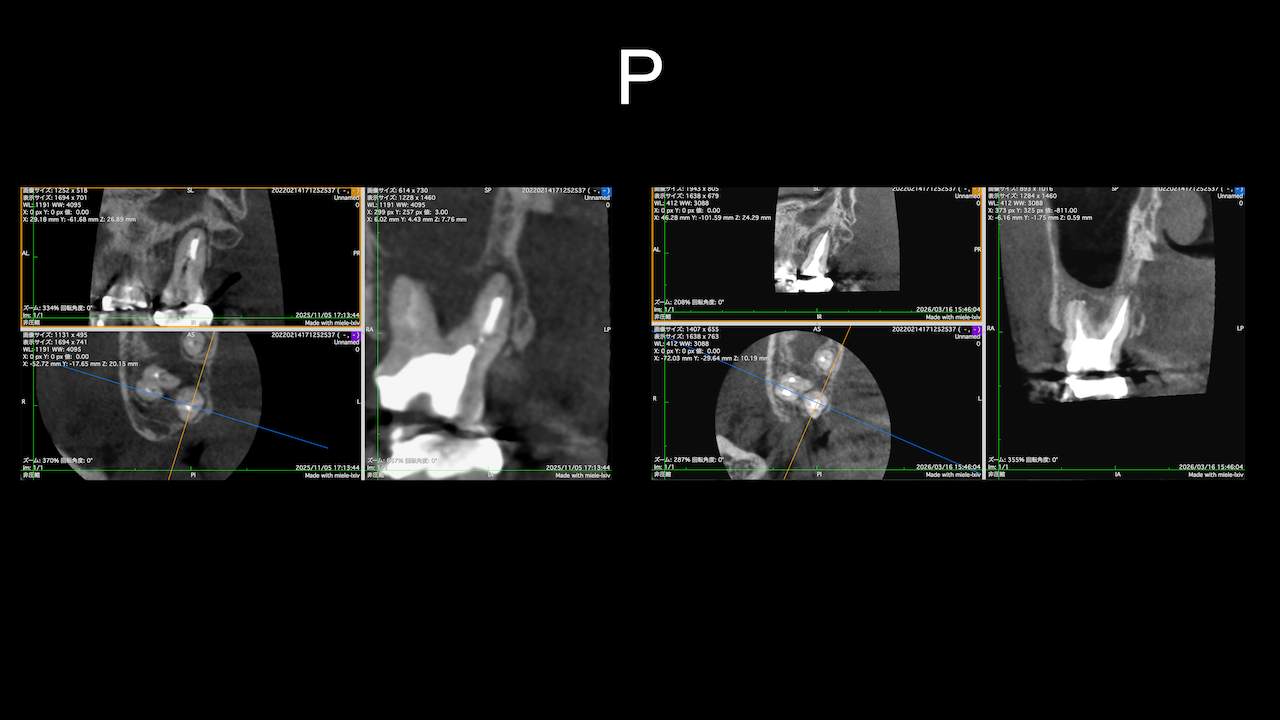

もう1ケースが以下だ。

#7がCold testに無反応である。

故に、#7,8の非外科的根管治療を行うことになった。

が、#8のメタルコアは外しにくいだろう。

CBCTでは2本とも口蓋側の皮質骨が消失している。

という絶望的な状況である。

が、

術前にその予後を患者さんに説明し、

治療へ移行した。

その結果、

ここから4ヶ月が経過すると…

臨床症状も皮質骨も大きく治癒している。

1年後の予後が気になるところであるが、すごくよくマネージメントできているだろう。